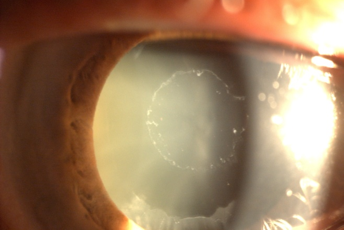

Su principal asociación en el ojo es el glaucoma (la probabilidad de desarrollar glaucoma en 10 años es del 45%), pero repercute en otras estructuras oculares dando lugar a sinequias posteriores, alteraciones corneales, subluxaciones del cristalino y debilidad zonular… contribuyendo todo ello a un mayor fracaso en la cirugía de catarata. En la siguiente imagen vemos el típico aspecto de ceniza o “caspilla” sobre la superficie anterior del cristalino.

Subluxación de cristalino en la que podemos apreciar material pseudoexfoliativo en la zónula.